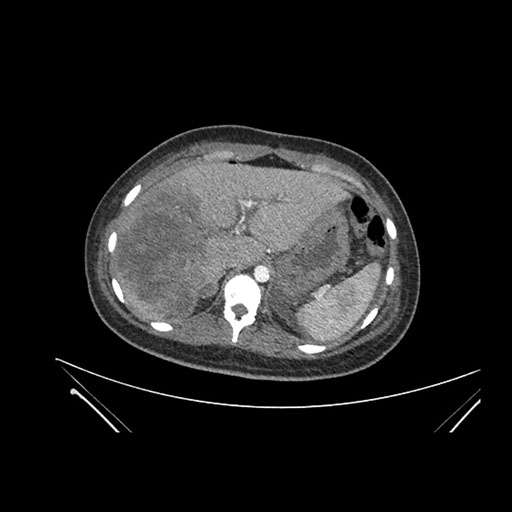

Axial Venous

Imaging analysis

Based on initial findings, which issue(s) would you be most concerned about?